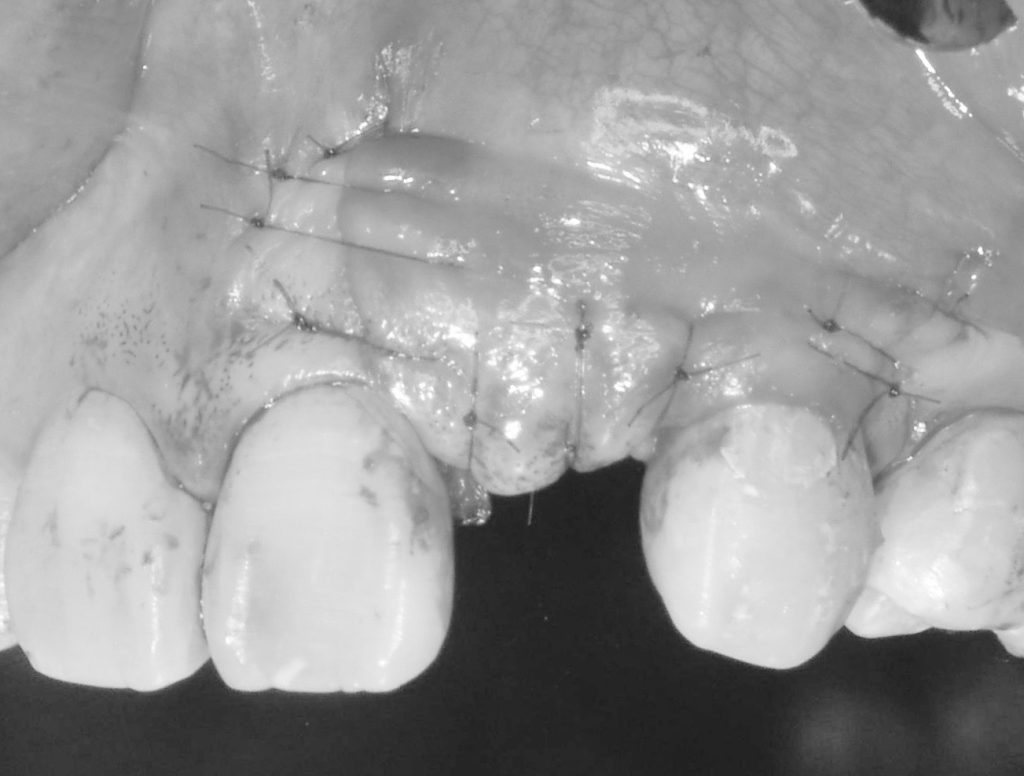

その為、当医院では様々な骨造成手技を用い、長期的に安定したインプラント周囲骨そして、審美的な結果を左右する結合組織移植を同時に行い、周囲環境を改善していきます。

GBRを伴うインプラント治療の費用 約70万円(税別)